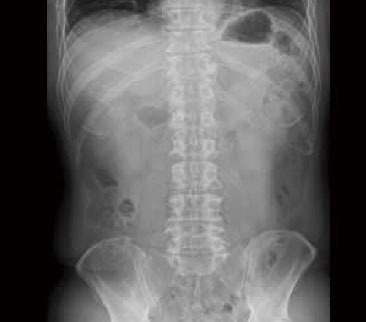

一般撮影

一般撮影とは

一般撮影は、レントゲン検査やⅩ線撮影と呼ばれることもあり、胸部、腹部、骨など全身各部位の撮影を行います。

Ⅹ線という放射線を人体に照射して透過したⅩ線を画像にします。

検査時間は、部位や撮影回数により異なりますが5~10分程度です。

腹部